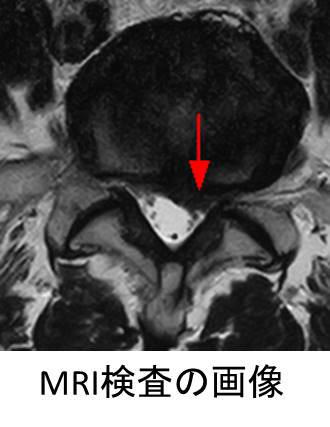

腰椎椎間板ヘルニア